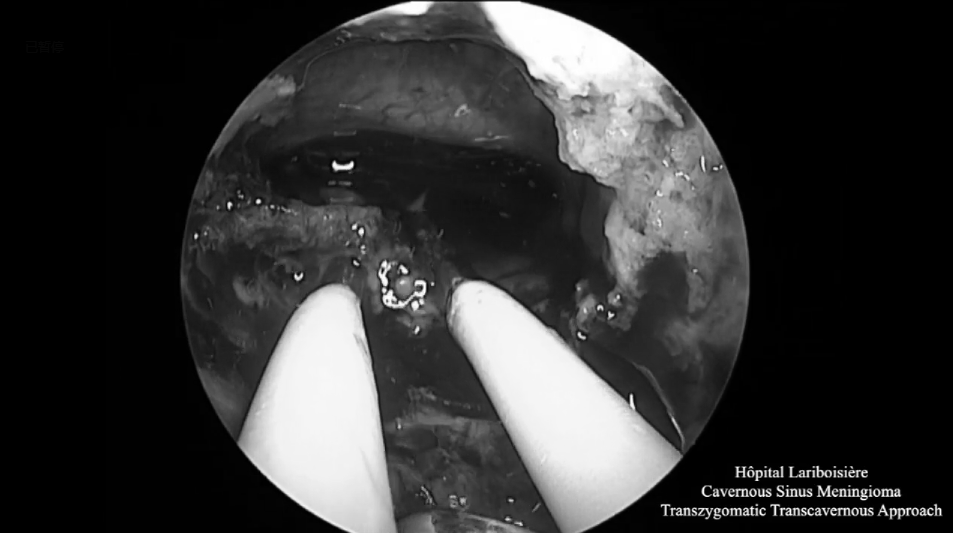

▼神經(jīng)內(nèi)鏡操作下暴露和切除腫瘤

神經(jīng)內(nèi)鏡操作下暴露和切除腫瘤

▼神經(jīng)內(nèi)鏡下切除腫瘤后的術(shù)野

神經(jīng)內(nèi)鏡下切除腫瘤后的術(shù)野

▼術(shù)腔使用自體脂肪填充

術(shù)腔使用自體脂肪填充